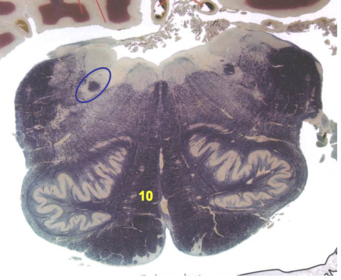

| Nucleus gracilis | |

| Accessory nucleus | |

| Medial longitudinal faciculus | |

| Pyramidal decussation | |

| Medullary pyramids | |

| Anterior spinocerebellar tract | |

| ALS | |

| Posterior spinocerebellar tract | |

| Spinal tract of V | |

| Spinal nucleus of V | |

| Nucleus cuneatus | |

| Fasciculus cuneatus | |

| Fasciculus gracilis | |

| Central canal | |

| Internal acruate fibers | |

| Lateral (external/accessory) cuneate nucleus | |